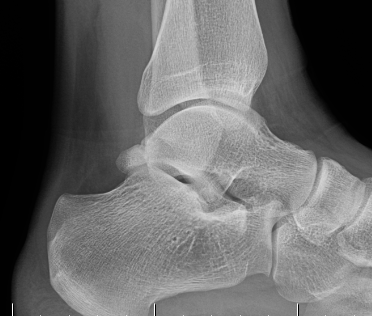

Xray

Os trigonum

Stieda process - elongated lateral process of talus